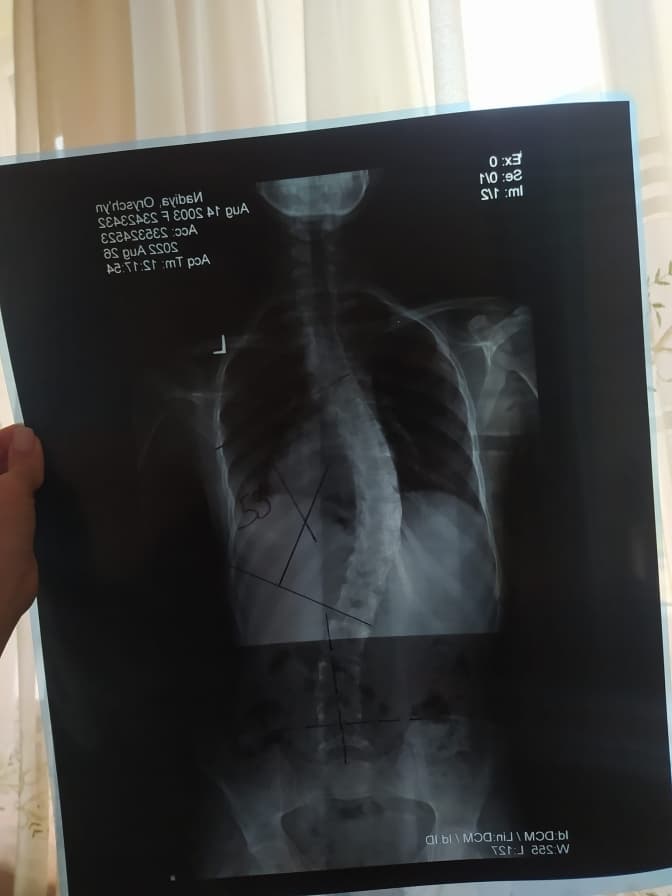

Львів’ян закликають долучитися до допомоги 19-річній Надії Орищин з підлітковим ідіопатичним сколіозом. Вона навчається в Луцьку, але родом з Червонограда на Львівщині. Такий діагноз їй поставили у 2019 році.

За її словами, хвороба прогресує і потребує негайного оперативного втручання. Вартість становить 250 тисяч гривень, і вже є спеціалісти, які можуть зробити операцію в Україні. Картка мами: 5168 7451 2316 5075 (Приватбанк), картка Надії: 5375 4114 2035 6508.

Фото Надії Орищин